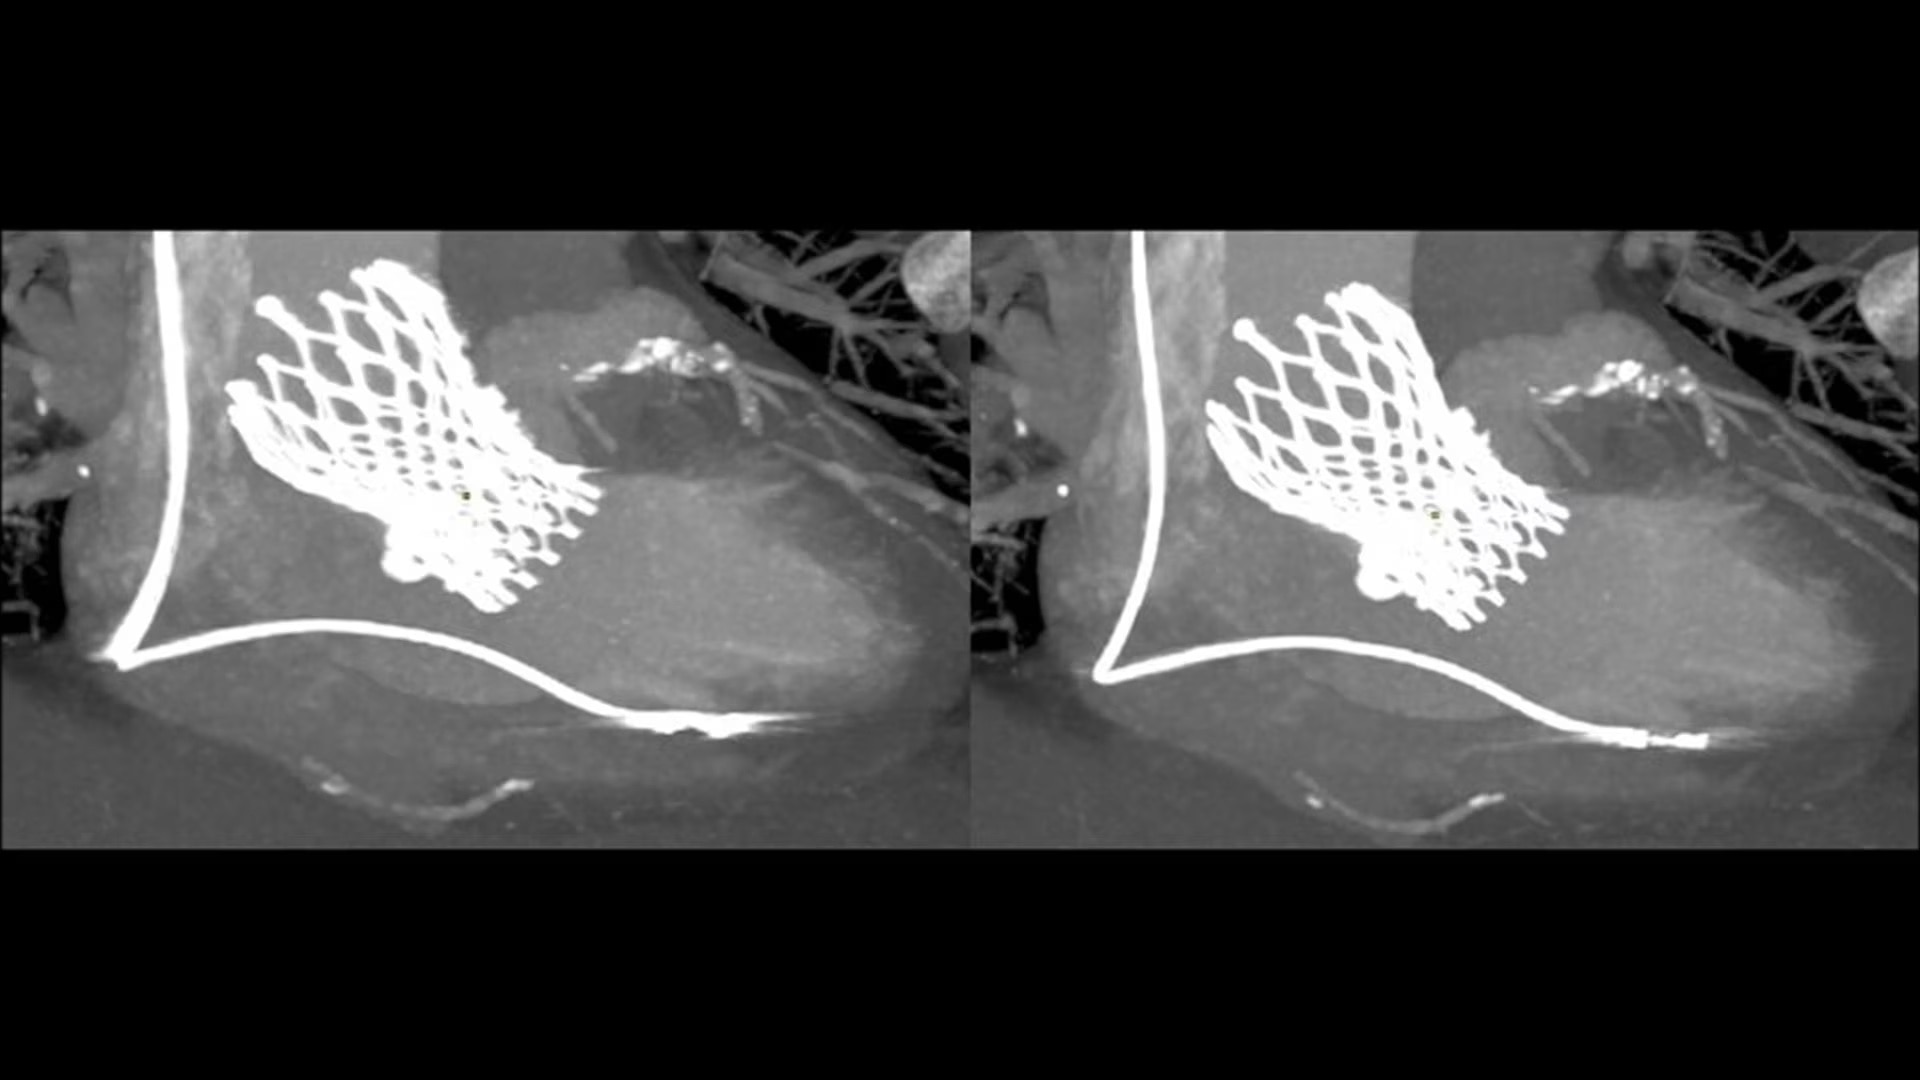

SnapShot Freeze 2

Intelligent and automated whole-heart motion correction for enhanced Cardiac CT imaging.

Motion correction

6x reduction in motion artifacts1